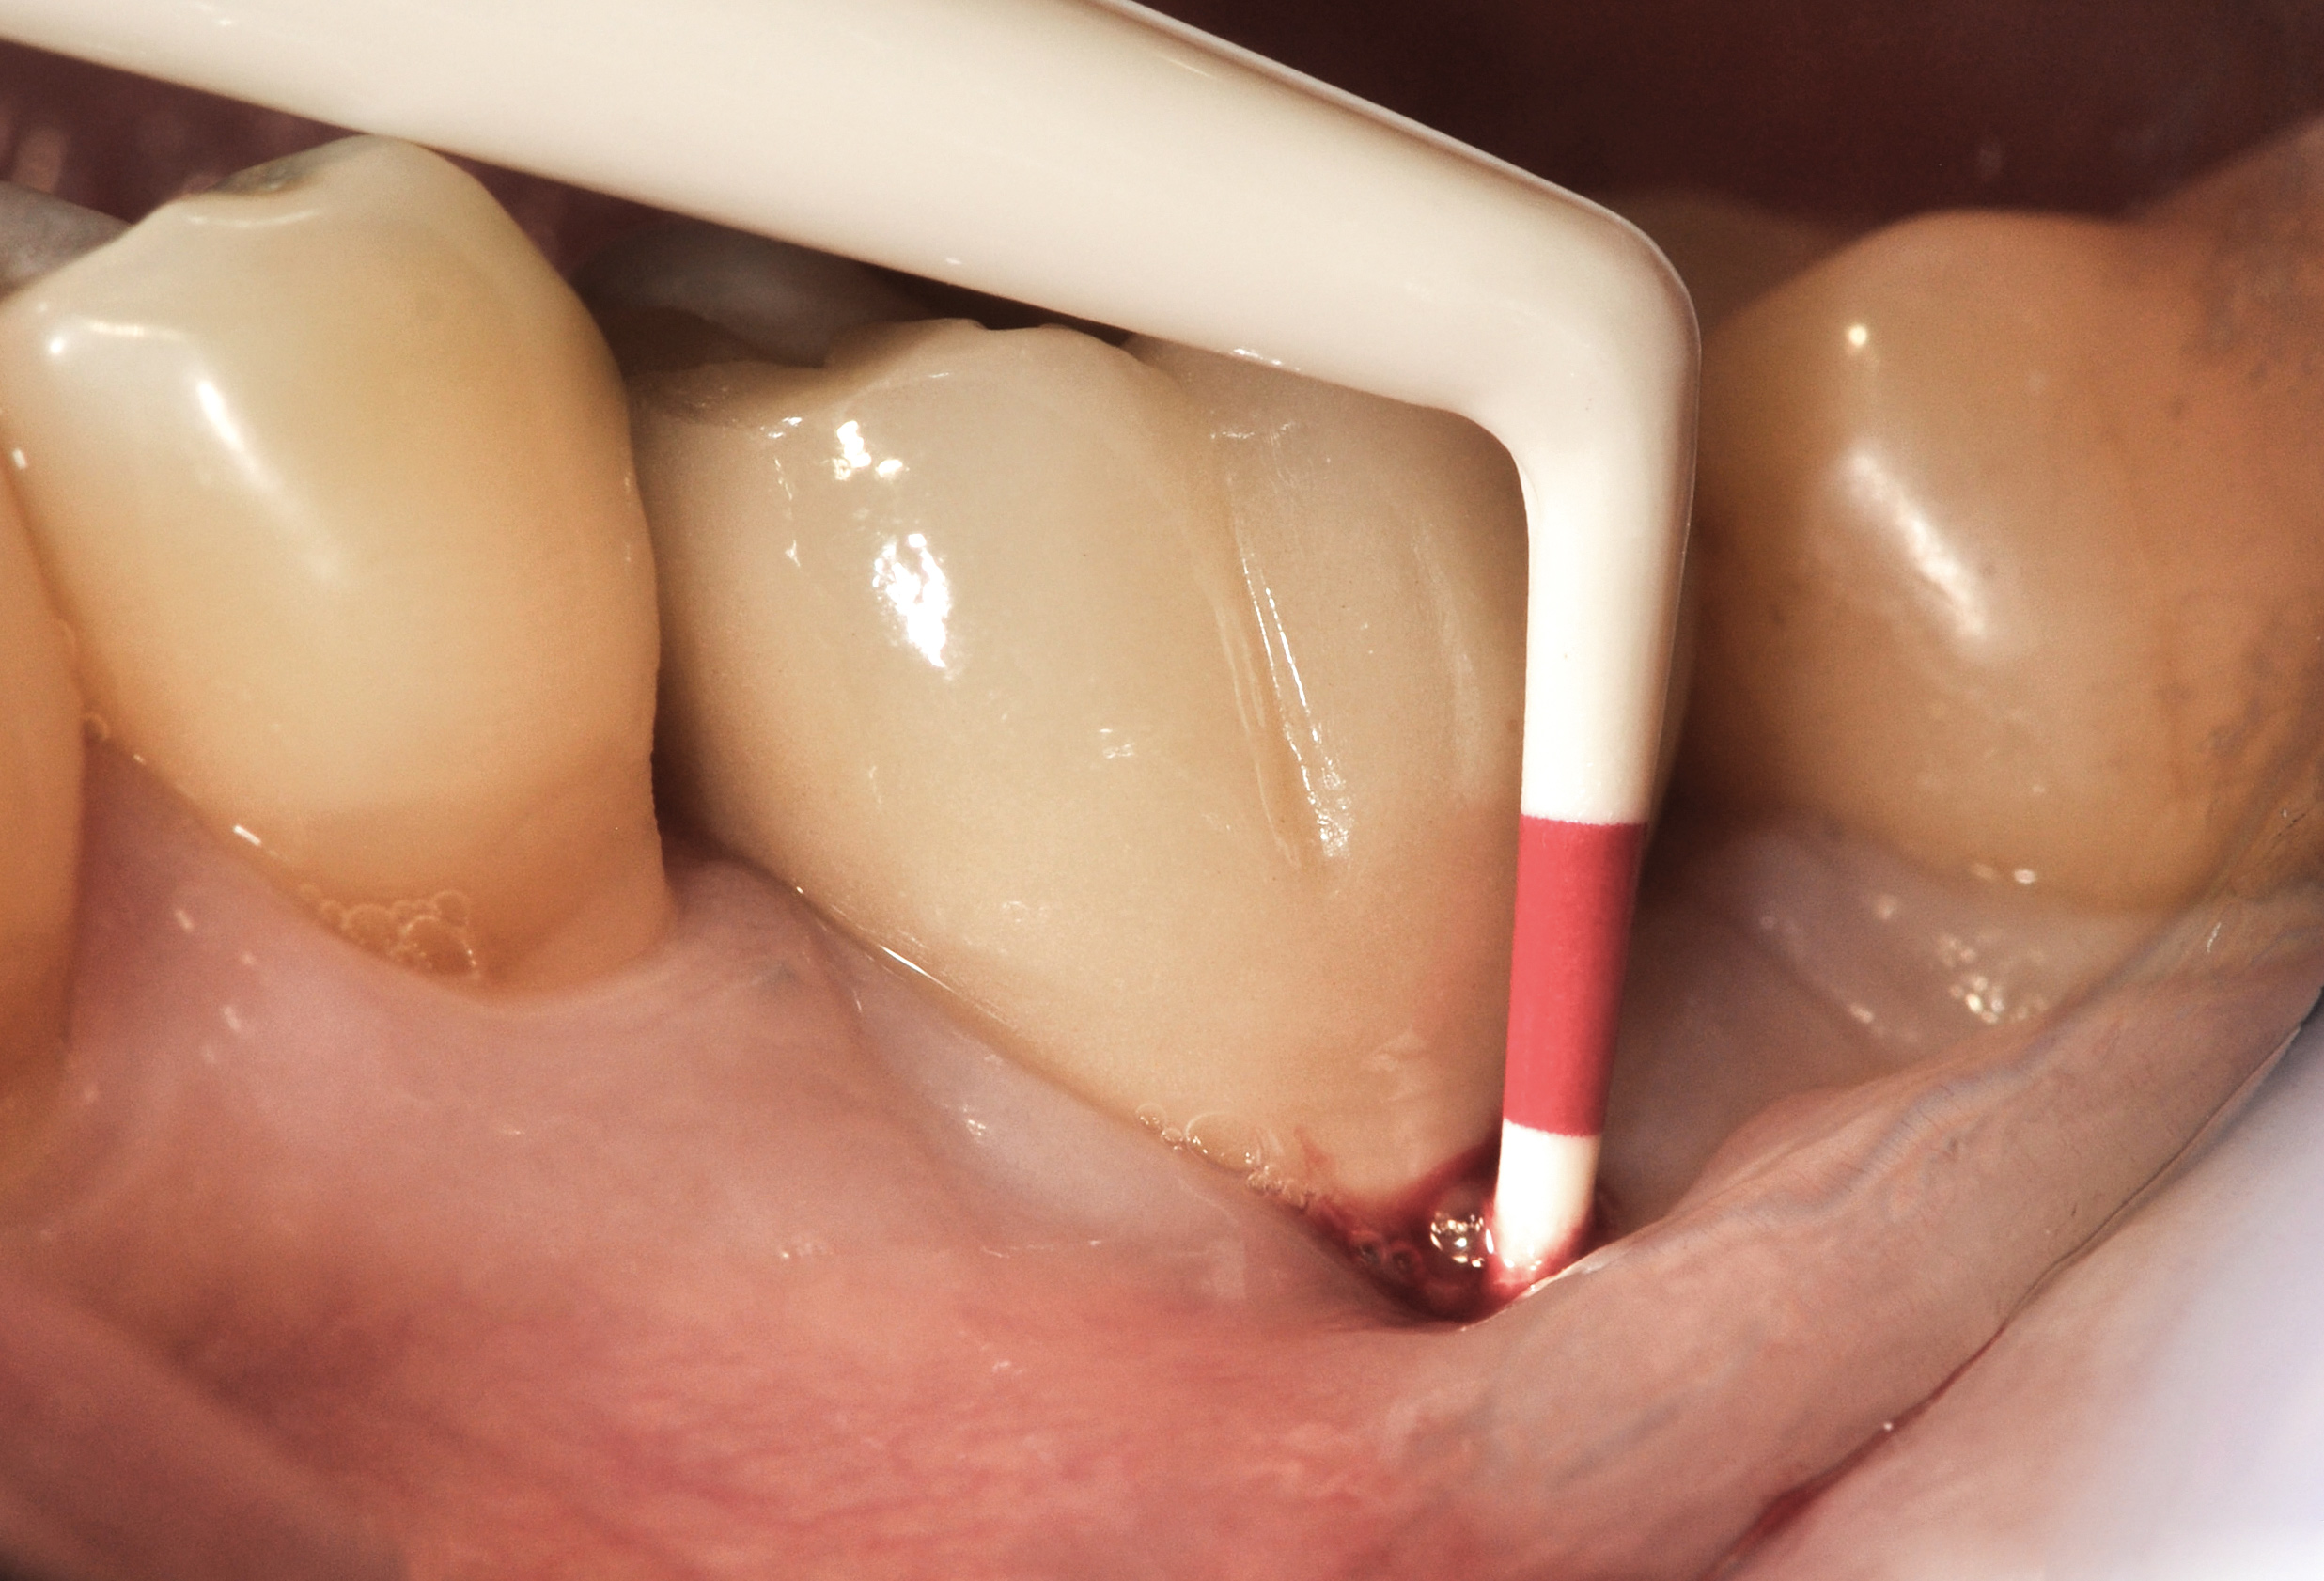

Fig 15. The implant-supported restoration of tooth No. 19 presented with a lack of attached keratinized gingiva, shallow buccal vestibule, and 2 mm of buccal recession.

Figure 15

Fig 16. The restoration exhibited an 8-mm pocket upon probing, with bleeding on the buccal aspect.

Figure 16

Clinical examination showed 2 mm of buccal recession with a shallow vestibule and absence of keratinized attached gingiva against the crown with 8 mm of circumferential pocketing accompanied by bleeding upon probing (Figure 15 and Figure 16). A periapical radiograph showed a symmetrical vertical osseous defect causing the loss of 50% of the bone around the implant (Figure 17). Because the patient had made a significant investment of time and finances to replace her lost tooth with the implant, she desired that the implant and restoration be retained, if feasible.